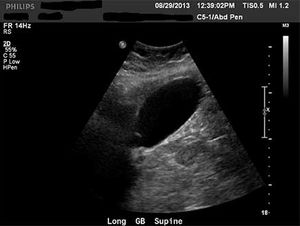

Clinical History: A woman in her mid-60s presented with right upper quadrant abdominal pain. An abdomen complete exam was ordered to rule out gallbladder disease. The patient had no history of smoking or diabetes.